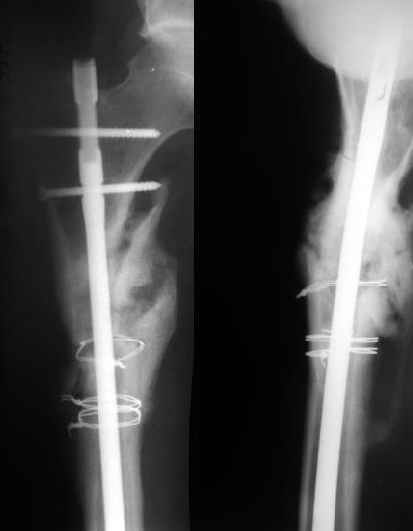

1) Мы бы не убирали проволоку, и вообще не вмешивались открыто на очаге - это ничего не даст, кроме ухудшения кровоснабжения концов отломков. Если просто закрыто перештифтовать при подобной картине, лучше с рассврливанием - это по нашему опыту дает сращение в 100%. В приложении пример - болезненное несращение более года, результат через полгода.

1

2